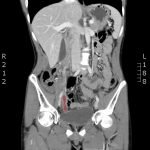

The CT abdomen/pelvis with intravenous contrast shows a dilated appendix (see red outline) with thickened, hyperenhancing wall (see blue outline) best visualized in the axial and coronal planes.